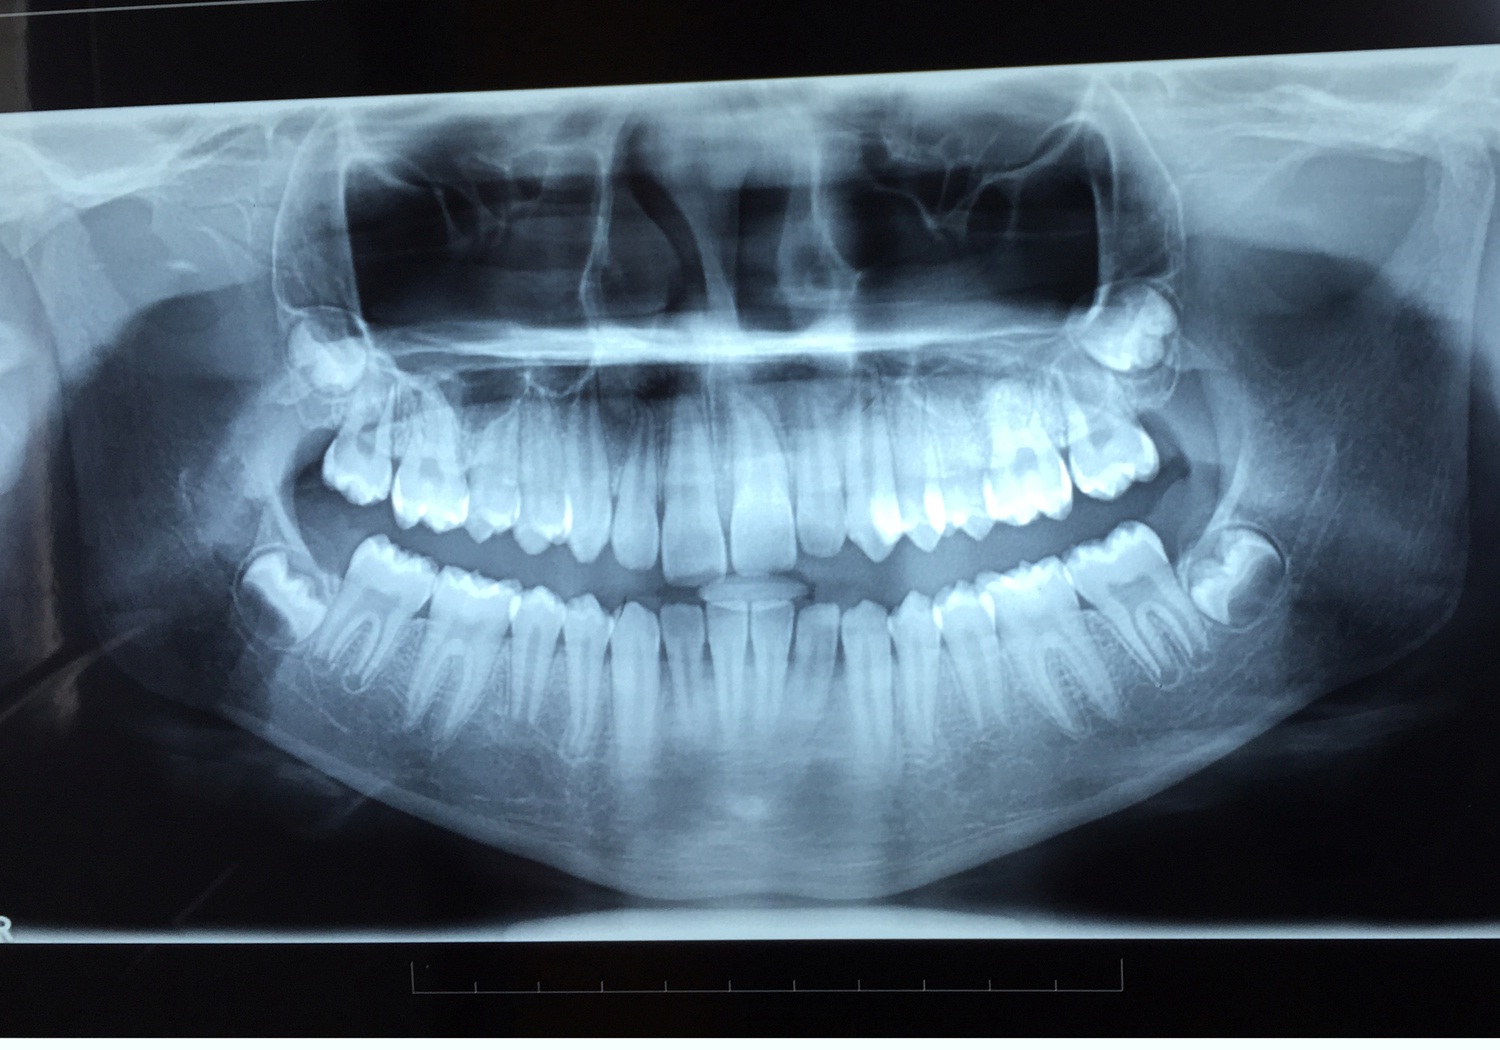

A 12-year-old female patient reported to the Department of Orthodontics of Maulana Azad Institute of Dental Sciences, New Delhi with chief complaint of missing upper front tooth. On clinical examination it was found that maxillary left central incisor (21) was missing [Table/Fig-1]. No significant history of trauma or premature/delayed shedding of primary left central incisor was reported. Panoramic and maxillary occlusal view revealed impacted left central incisor with dilacerated root [Table/Fig-2,3]. Since the contralateral central incisor had erupted fully in the mouth and the root formation of the impacted central incisor was almost complete, it was decided to disimpact the tooth (21). Disimpaction was planned by surgical exposure followed by elastic traction with the help of removable appliance. Since the patient had well aligned upper and lower arches in good occlusion, it was decided to use a modified removable appliance for extrusion of 21. A removable appliance with modified labial bow was fabricated. Labial bow in the anterior region was fabricated with 22 gauge wire and helices were incorporated in the labial bow adjacent to left central incisor region. Retention was provided by the acrylic coverage in the palatal region and by well formed retentive clasps. Surgical exposure of left central incisor was performed by open exposure technique. A bondable button was placed onto the labial surface of exposed left central incisor crown [Table/Fig-4]. Patient was trained to use elastic in triangular fashion to engage button on 21, and two helices of the labial bow, which resulted in an extrusive force of 20 grams for disimpaction of 21[Table/Fig-5] [1]. Patient was advised to change the elastic daily and was reviewed every three weeks. At the end of six months, complete disimpaction of 21 was achieved with the tooth in its optimal alignment into the upper dental arch and in good relation with lower teeth [Table/Fig-6,7]. Post disimpaction panoramic view reveals tooth 21 in the optimal position with respect to maxillary occlusal plane [Table/Fig-8].

Pretreatment panoramic and maxillary occlusal view showing vertically impacted maxillary left central Incisor with dilacerated root.

Post treatment panoramic view.